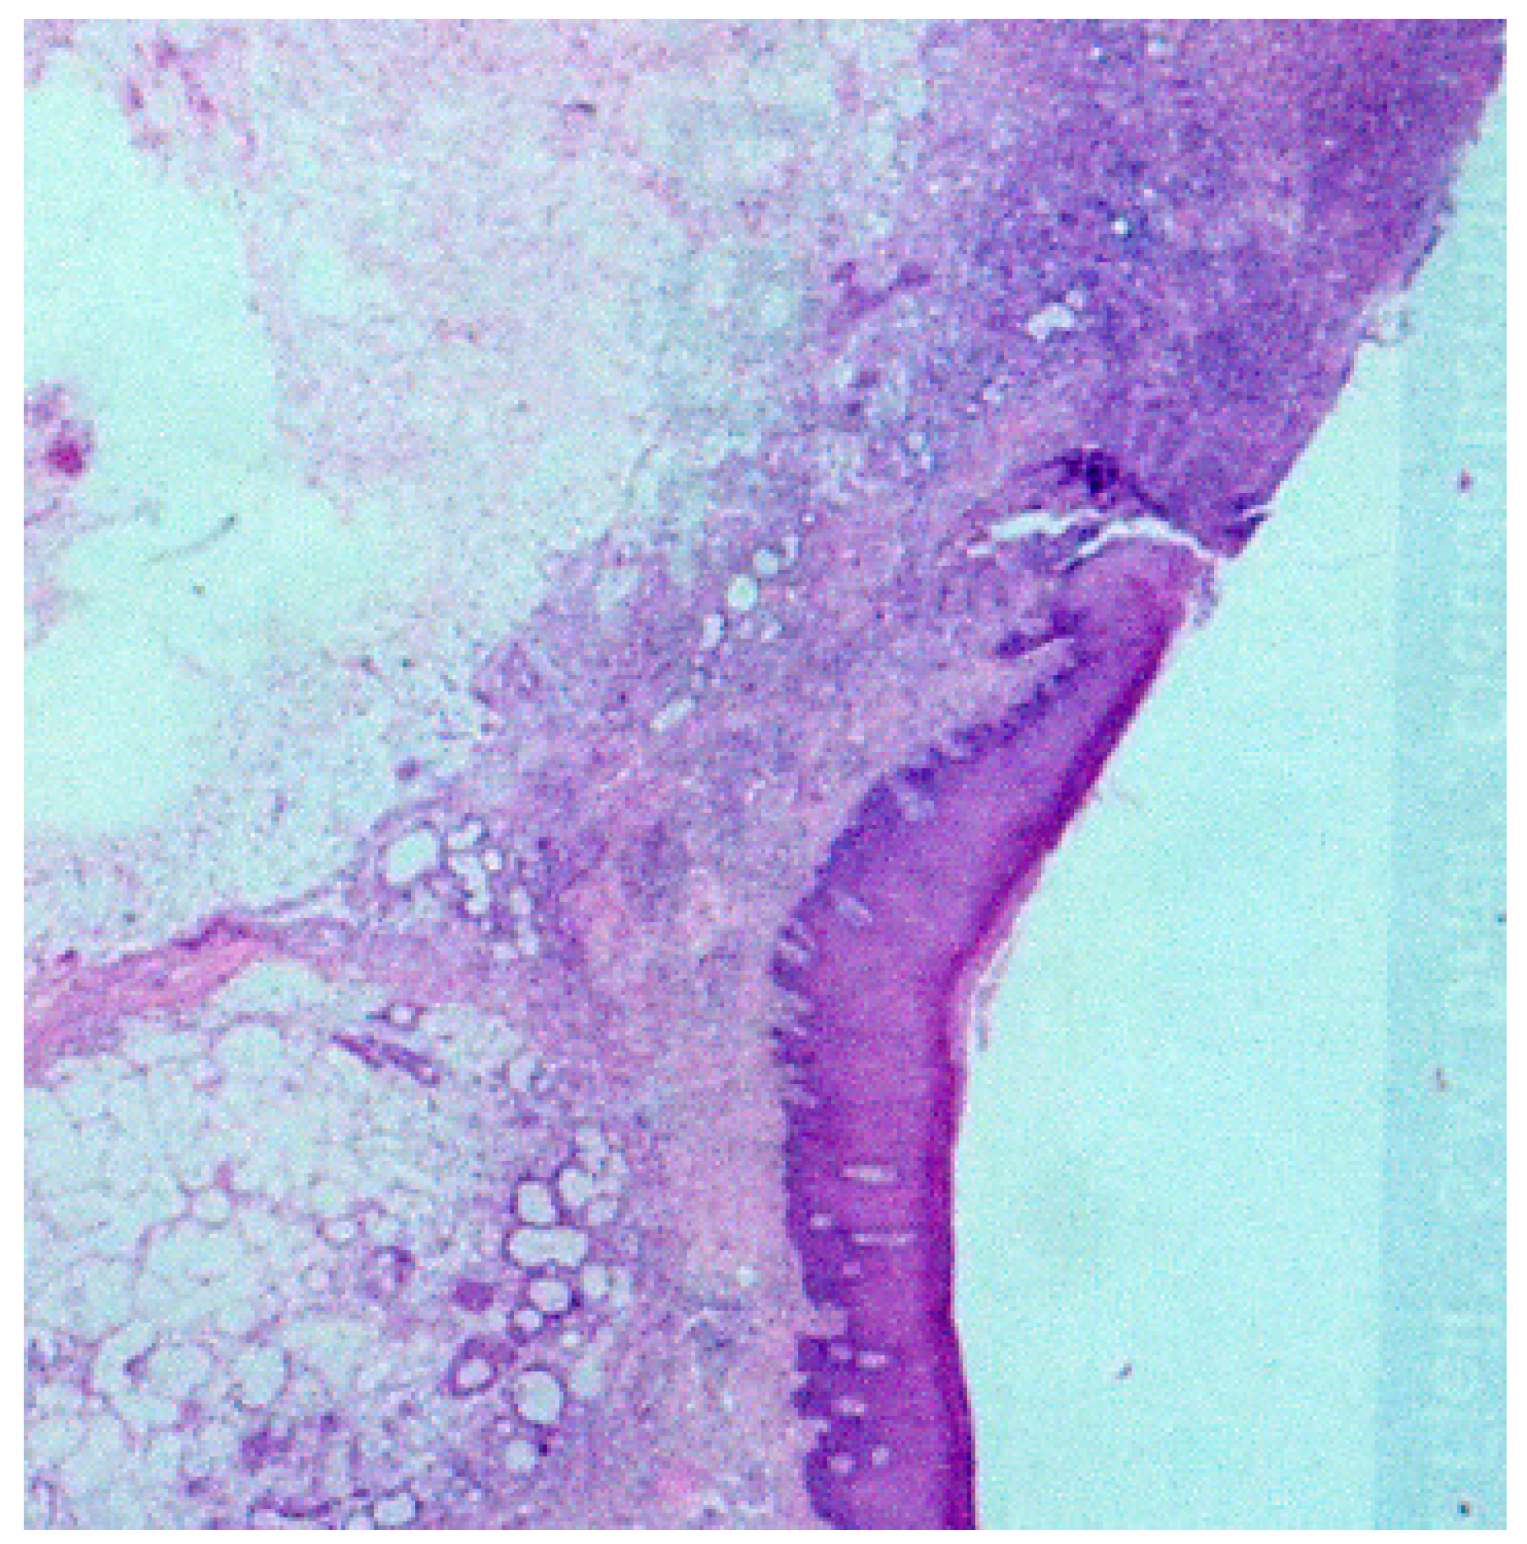

2. Case Report